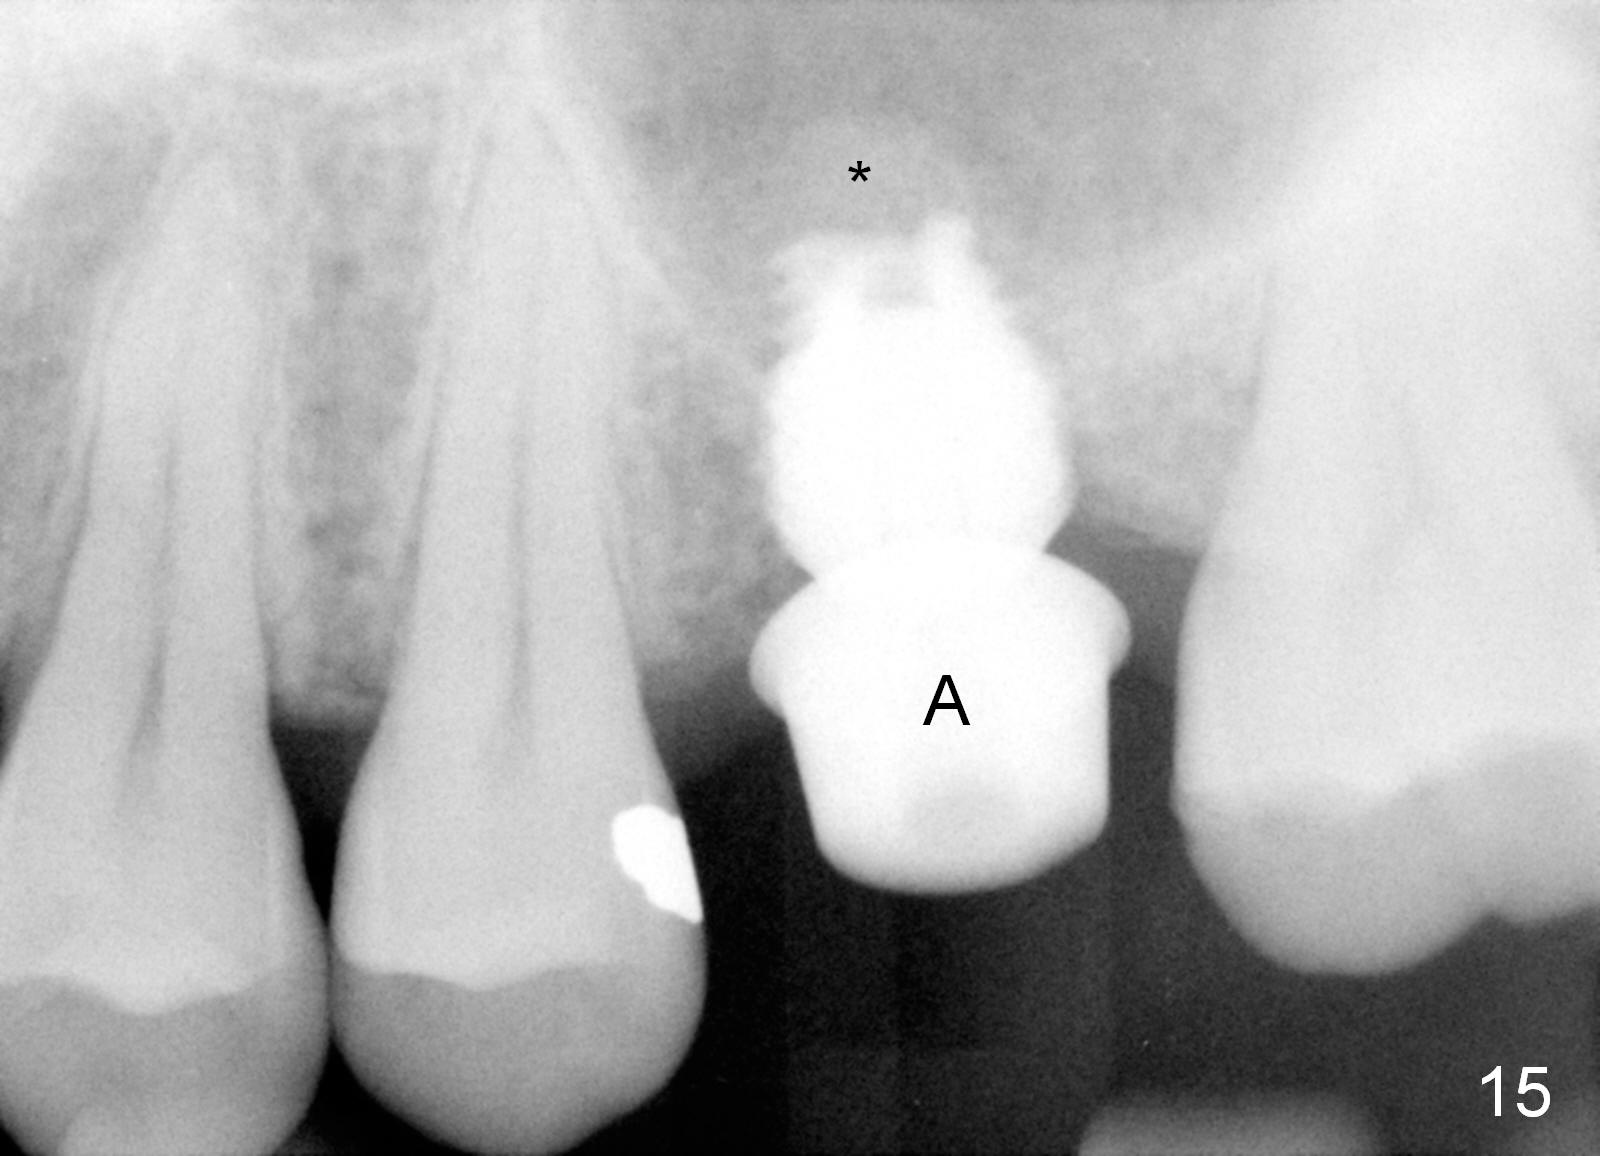

A 45-year-old man has lost the tooth #14 for a while (Fig.1); bone height is 5.4 mm. An extra wide and short implant is planned. Torus palatinus is large, suggesting that bone density should be high. A 6 mm tissue punch is chosen, but it is placed more palatal. If it were placed in the middle of the ridge, there would be no buccal keratinized gingiva (incision may avoid this issue). Additionally, the buccal portion of punch is made incomplete so that there is pedicle on the buccal side when the flap is raised (Fig.4,8: F). It is expected that the excess portion of keratinized tissue will form thick gingiva buccally. Osteotomy proves that bone is dense (Fig.2 (4.5x11 mm tap). Typical sinus lift is finished with placement of 6.4x6 mm (extra wide) bone-level implant (Fig.3, >55 Ncm). Following further torque, Fig.4 shows that the implant (I) is sub-gingival (<). Bitewings are taken to confirm that the implant plateau is at the crestal level (Fig.5,6 ^). PA shows sinus lift (Fig.7 *). The lingual aspect of the implant and healing abutment (H) is further bone grafted and covered by collagen dressing (Fig.8 *). The wound is protected with perio dressing. When the latter dislodges 7 days postop, the collagen dressing and bone graft are lost as well (Fig.10), while the buccal flap remains vital (Fig.9). The lingual exposed plateau should be able to heal normal. The collagen dressing should have been fixed in place by suture or as simple as a dental floss. There is mild nasal hemorrhage 1-2 days postop, possibly related to sinus membrane perforation and inability of Collagen Dressing to cover the perforation and contain the bone graft. When the patient returns for #9 implant placement in 3 weeks postop, the buccal flap reduces in size (Fig.11 *), while the palatal wound has healed with minimal exposure of the implant (Fig.12). Sinus graft remains in place 3 months postop (Fig.13); the buccal flap appears to have incorporated into a part of the gingiva (Fig.14). The bone density of the sinus lift appears to increase 10 days later when an abutment is placed (Fig.15 *). Although oral hygiene is pristine, there is apparent crestal bone resorption 12 months (Fig.16) and 20 months (Fig.17) post cementation, probably due to unfavorable crown/implant ratio and bruxism as well as pre-implantation bone loss (Fig.18,19). In contrast, an immediate implant in the same patient avoids pre- or post-implantation bone loss. In fact both the soft (Fig.20) and hard (Fig.21) tissues remain healthy 2 years 8 months post cementation. The sinus lift remains 3 years 8 months post cementation (Fig.22), while the crestal bone loss persists. The patients keeps complains of food impaction distal associated with bad smell 4 years 1 month post cementation. In fact the distal proximal contact is within normal limit. The bad smell is probably due to crestal bone loss (Fig.23 (pan), 24 (CT) *) and periimplantitis. Bone graft, PRF and Cytoplast membrane will be needed and fixed in place with long healing screw. When the patient returns for crown redo, he also reveals floss related gingival hemorrhage. There is pain associated with palatal sulcus probing with light gingiva erythema. Review of CT coronal section shows possible palatal (Fig.25 P) bone loss (*).